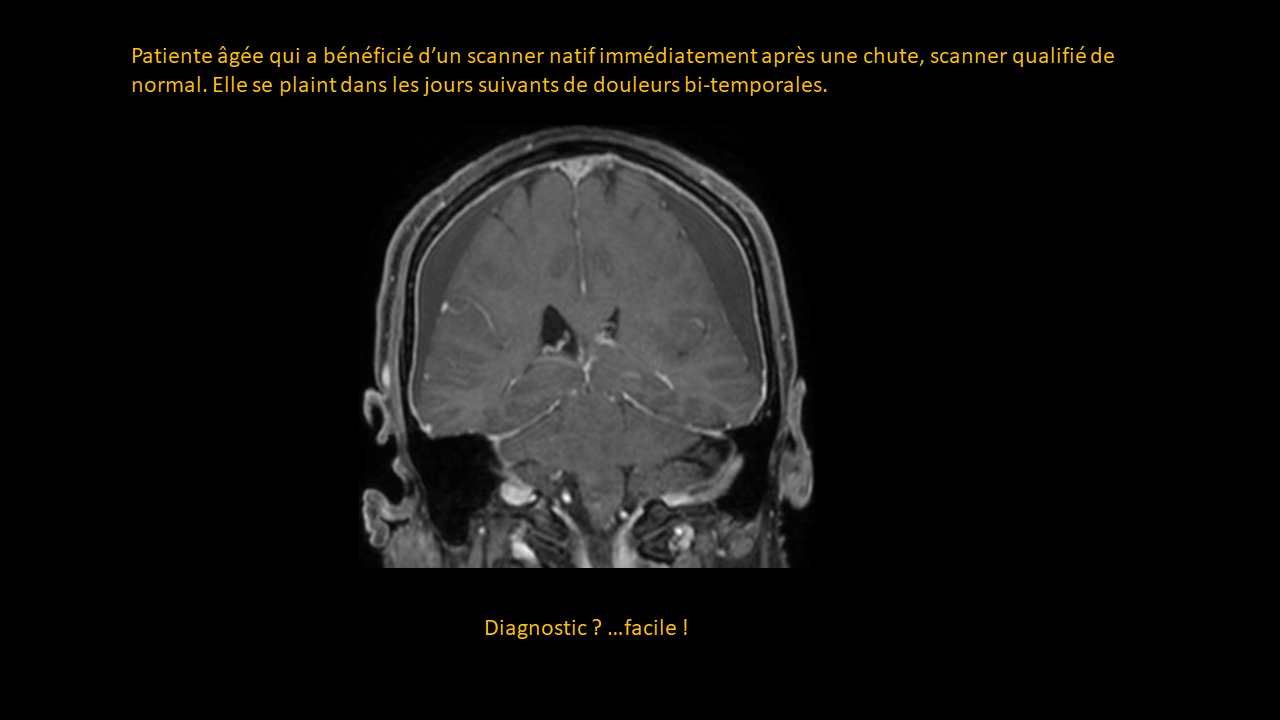

Système nerveux central